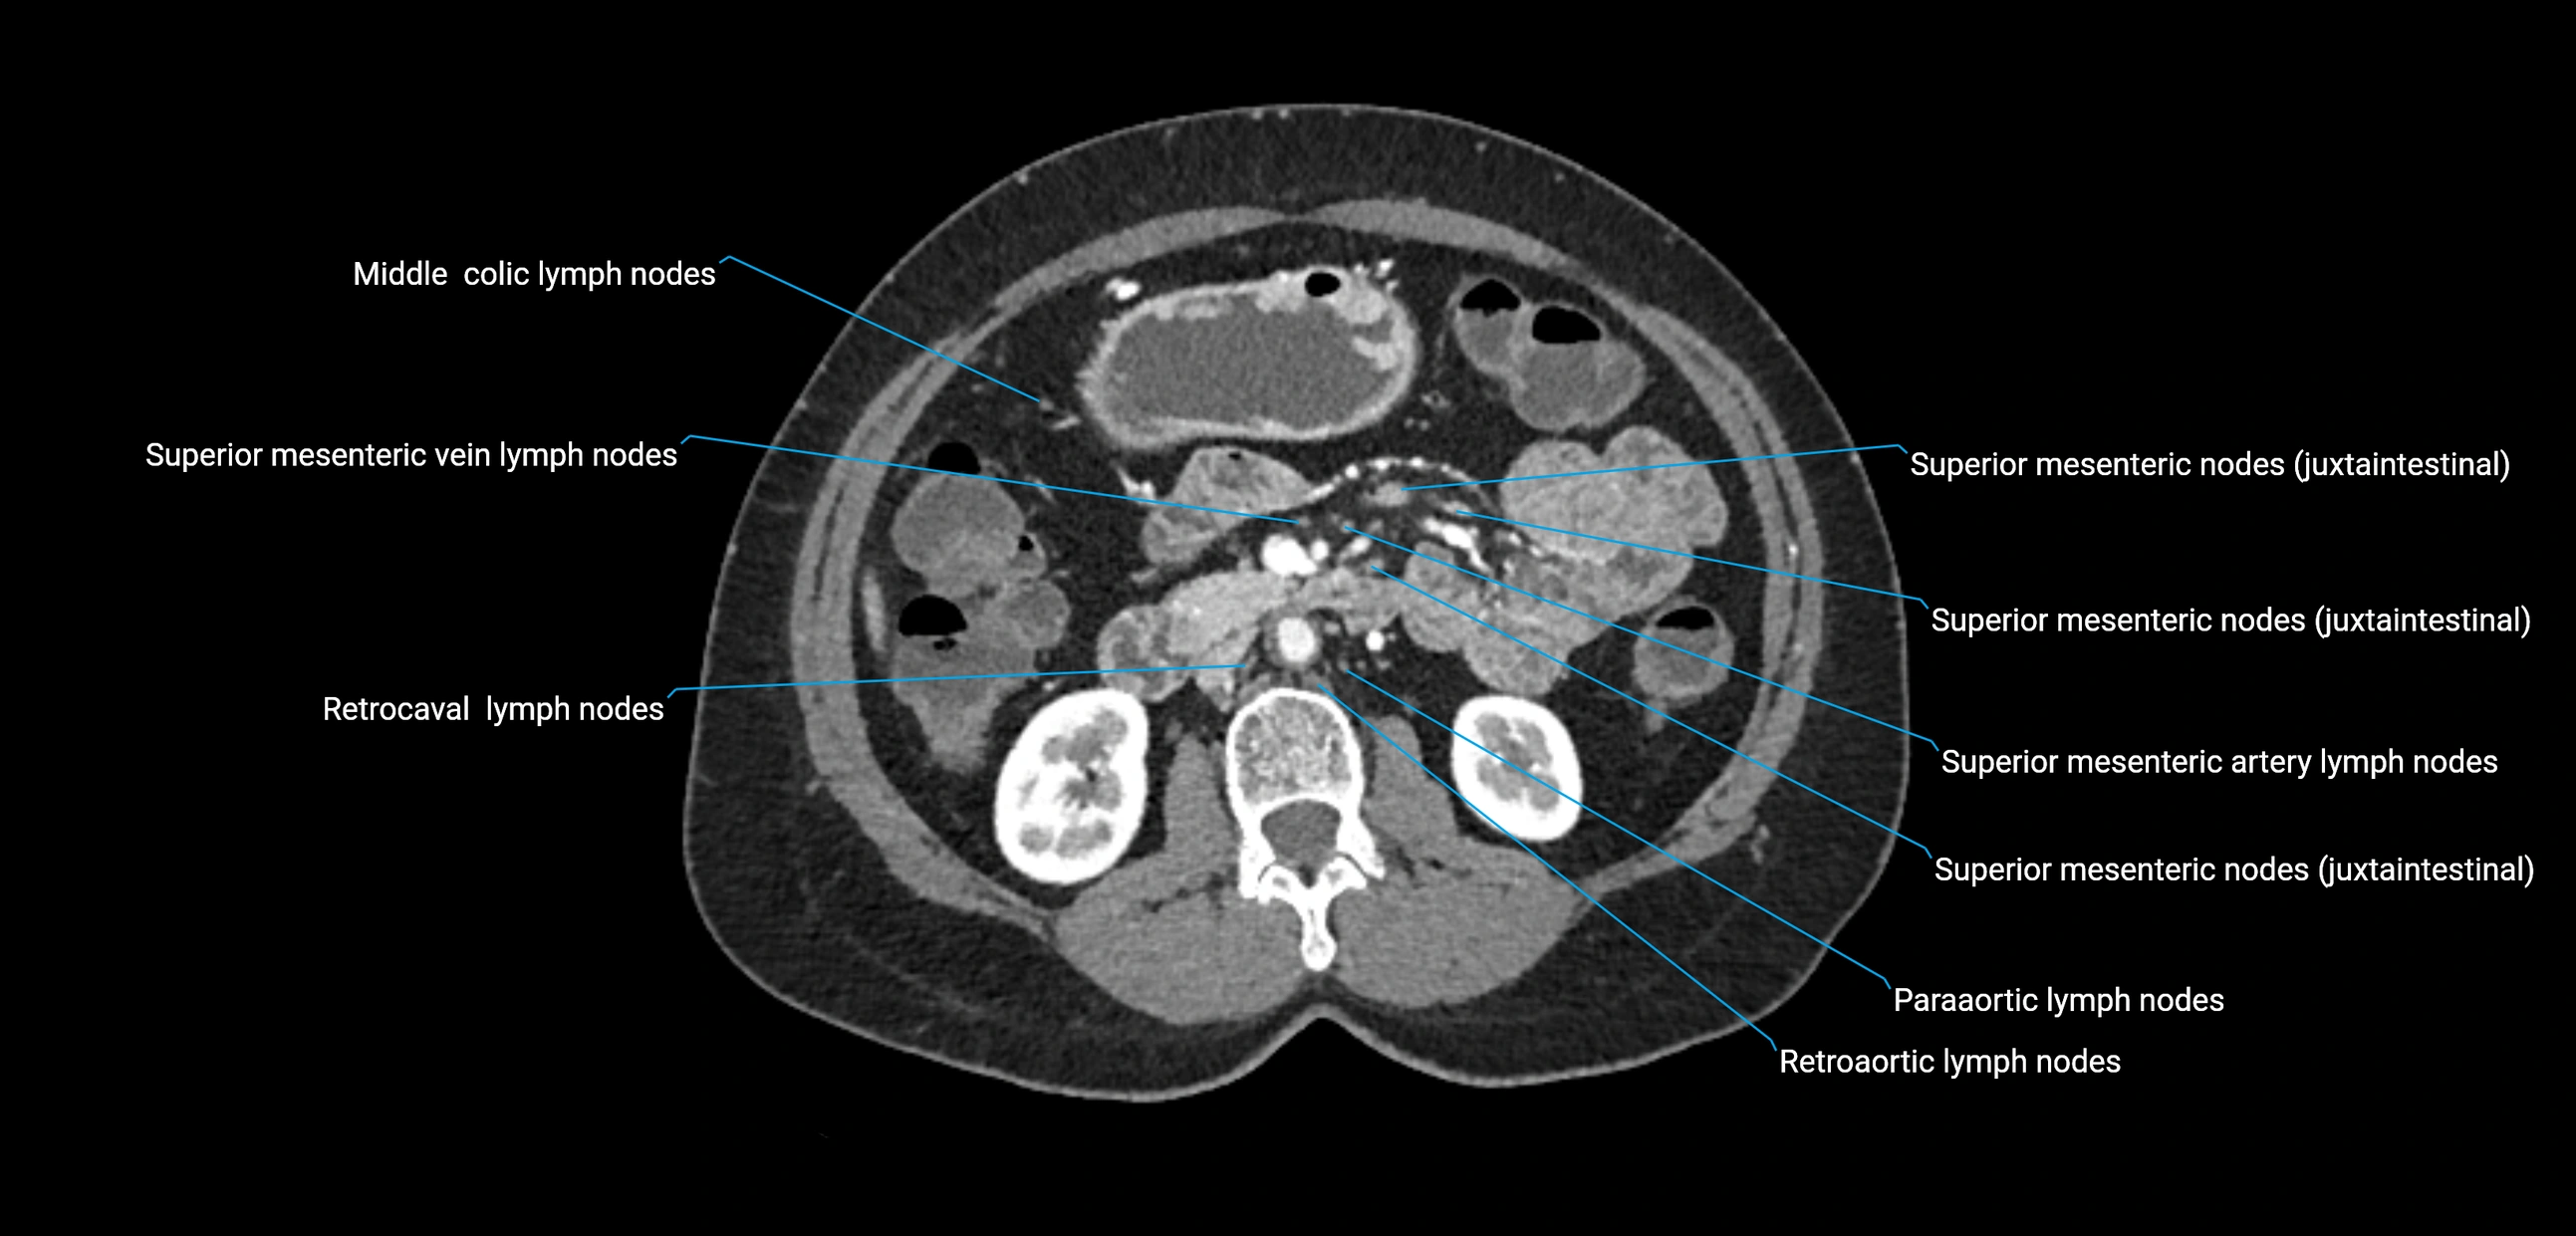

The lateral aortic lymph nodes (also called para-aortic lymph nodes) are a major group of retroperitoneal lymph nodes located along the abdominal aorta and its branches. They lie between the diaphragmatic crura superiorly and the bifurcation of the aorta at L4 inferiorly.

They are positioned on both sides of the abdominal aorta:

• Right lateral aortic nodes: adjacent to the inferior vena cava (IVC)

• Left lateral aortic nodes: lateral to the abdominal aorta

These nodes receive lymph from a wide range of abdominal and pelvic structures. Specifically, they drain lymph from the kidneys, suprarenal glands, gonads (testes/ovaries), uterus, uterine tubes, and pelvic organs, before converging into the lumbar lymphatic trunks, which terminate in the cisterna chyli → thoracic duct.

CT Appearance

CT Post-Contrast:

• Normal nodes enhance homogeneously

• Malignant nodes may show heterogeneous enhancement, central necrosis, or conglomerate formation

• Size >1 cm short axis is suspicious, though morphology and distribution are equally important

CT Venography (CTV):

• Demonstrates nodal encasement or compression of adjacent vessels (aorta, IVC, renal veins)

• Useful in staging testicular and ovarian malignancies

• Provides 3D reconstructions for retroperitoneal lymph node dissection planning